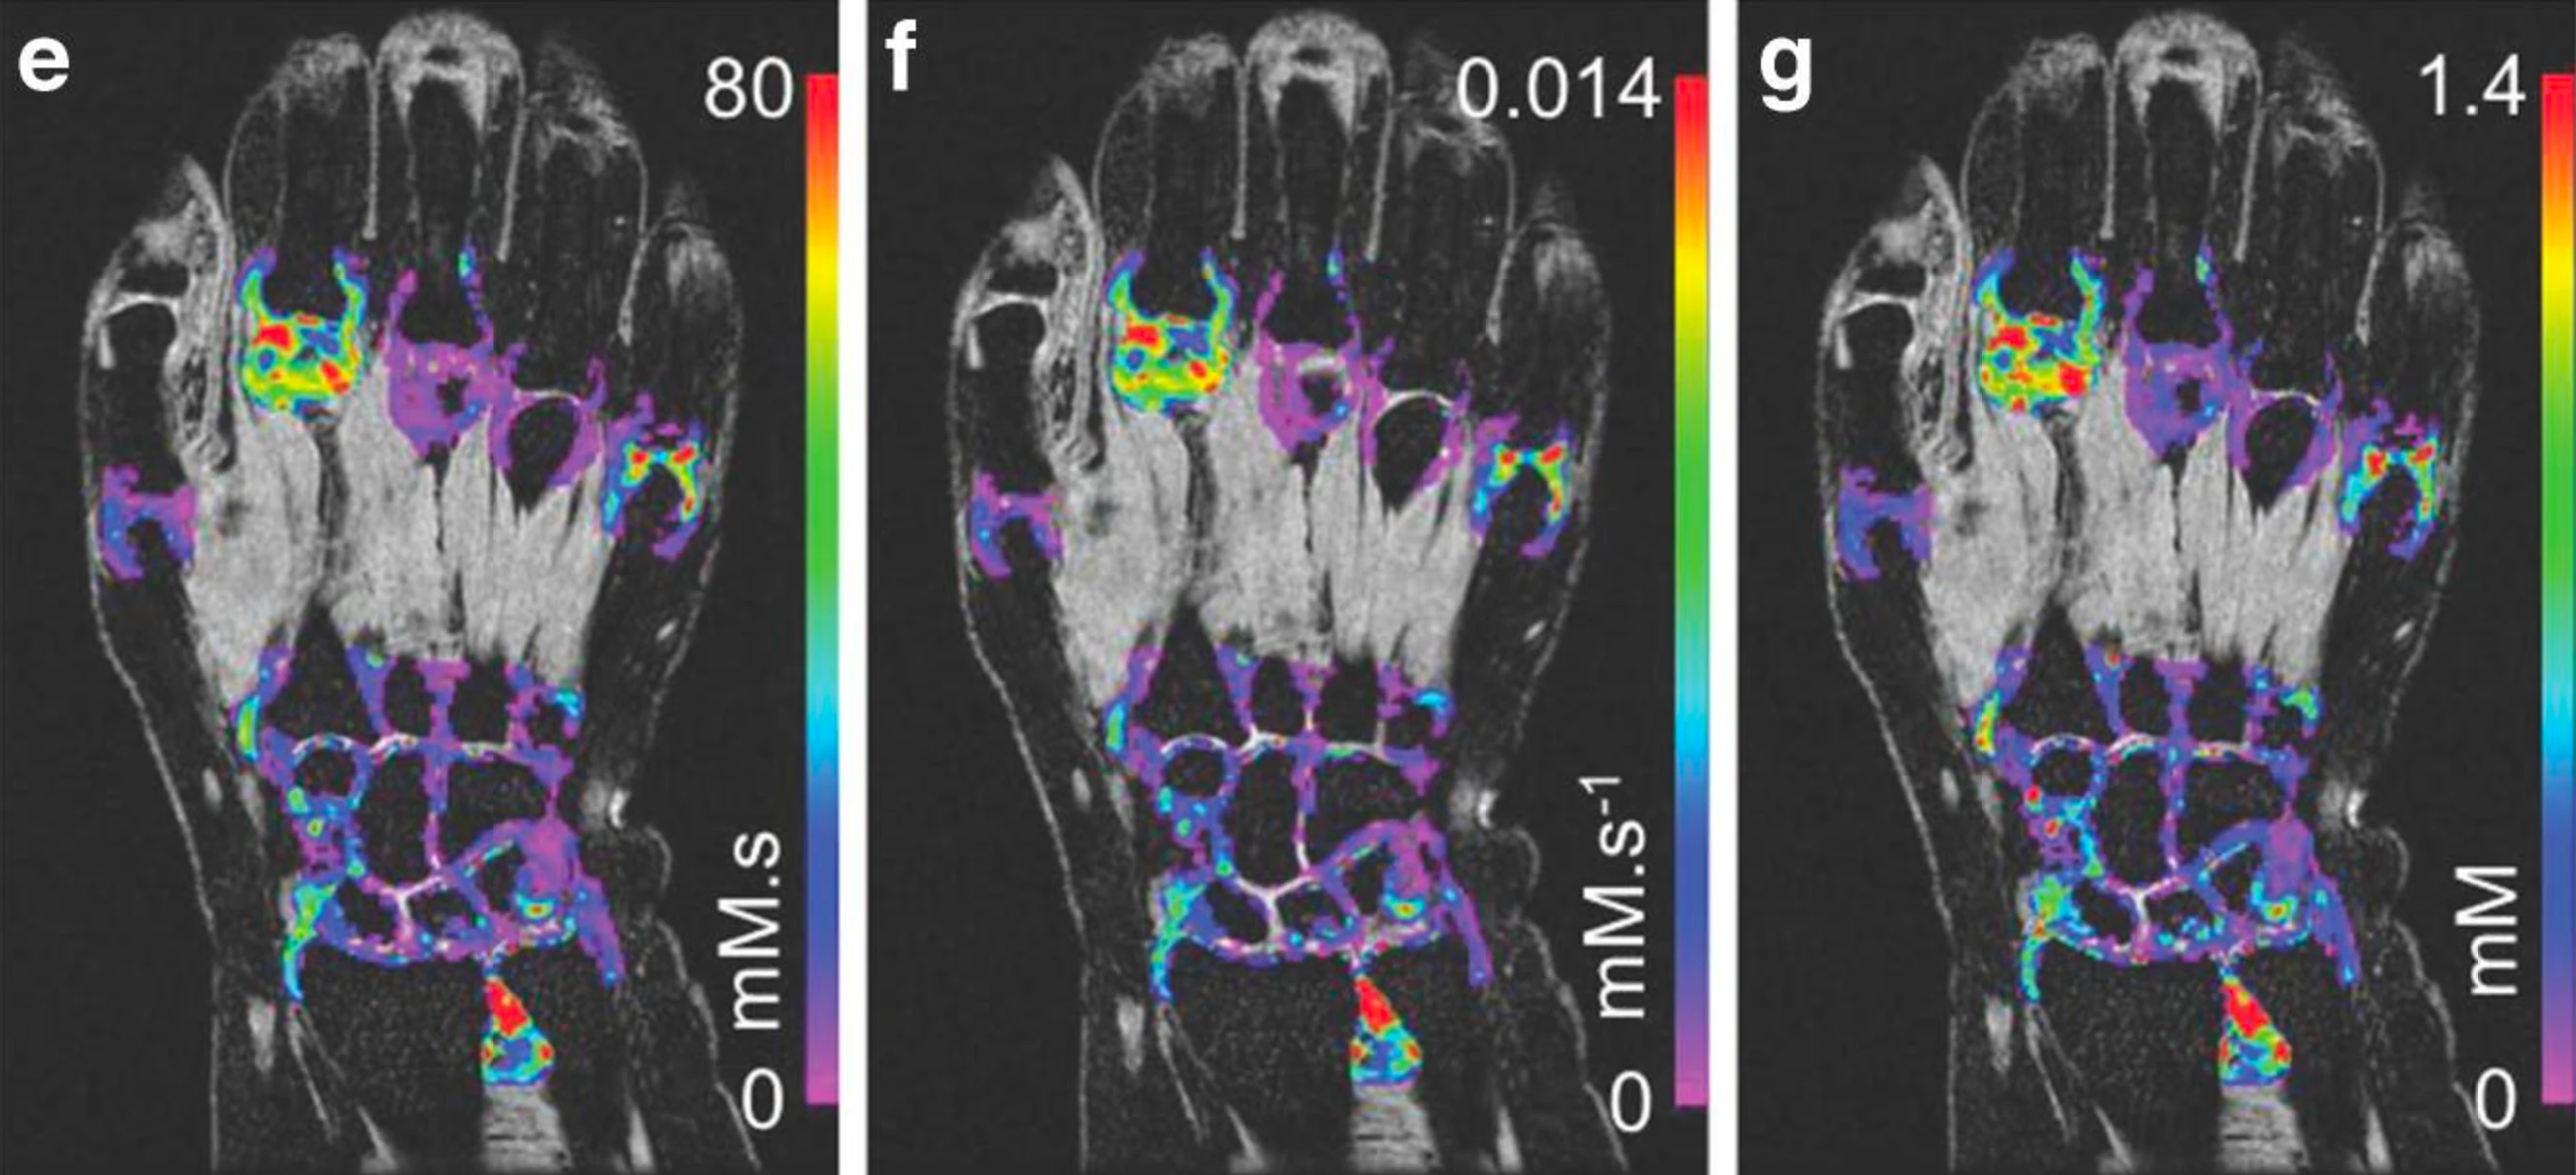

From study design to final reporting, Bioxydyn delivers repeatable MRI biomarkers that reveal tissue function, physiology and change. Our operational excellence and metrology help you compare results across sites, scanners and timepoints.

We're Bioxydyn - delivering quantitative MR biomarkers for pharmaceutical, biotech and academic studies. We combine scientifically leading methods with robust multi-centre study management and transparent analysis, turning complex images into repeatable measurements that support confident decisions.

Disease areas and services supporting quantitative MRI biomarkers across clinical trials.